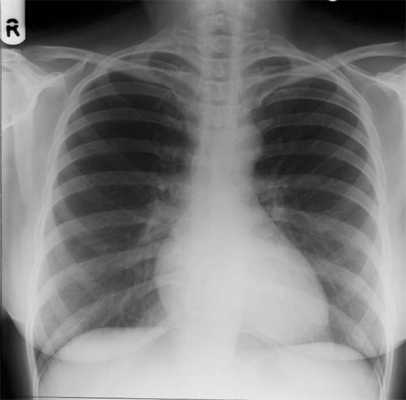

На рентгенограмме в прямой проекции сердце дает однородную интенсивную тень, располагающуюся посредине, но несколько асимметрично: примерно 1/3 сердца проецируется правее срединной линии тела, a Vi - левее этой линии. Контур тени сердца иногда выступает на 2-3 см вправо от правого контура позвоночника, контур верхушки сердца слева не доходит до срединно-ключичной линии. В целом тень сердца напоминает косо расположенный овал. У лиц гиперстенической конституции он занимает более горизонтальное положение, а у астеников - более вертикальное. Краниально изображение сердца переходит в тень средостения, которая на этом уровне представлена в основном крупными сосудами - аортой, верхней полой веной и легочной артерией. Между контурами сосудистого пучка и сердечным овалом образуются так называемые сердечно-сосудистые углы - выемки, которые создают талию сердца. Внизу изображение сердца сливается с тенью брюшных органов. Углы между контурами сердца и диафрагмы называют сердечно-диафрагмальными.

контуры сердечной тени, в норме ровные и четкие, имеют форму дуг. Каждая дуга представляет собой отображение выходящей на контур поверхности того или иного отдела сердца.

Все дуги сердца и сосудов отличаются гармоничной закругленностью. Выпрямленность дуги или какого-либо ее участка свидетельствует о патологических изменениях в стенке сердца или прилежаших тканях.

Рентгенограмма органов грудной клетки в прямой проекции. Обозначения: ЛЖ - левый желудочек, ПП - правое предсердие, ЛП - ушко левого предсердия, ЛС -легочной ствол, ДАо - дуга аорты, ВАо - восходящий отдел аорты.

В прямой передней проекции сердце и крупные сосуды занимают положение в средостении таким образом, что 2/3 сердечной тени находится слева, 1/3 - справа. Вдоль правого контура сердечно-сосудистой тени образуются две дуги. Верхняя дуга образована верхней полой веной (в некоторых случаях восходящей аортой). Нижняя - правым предсердием. По длине они соотносятся, как 1/1. Место схождения этих дуг называется правым атриовазальным углом. Расстояние от срединной линии до наружного контура первой дуги в этой проекции 3-4 см. Нижняя дуга правого контура в прямой проекции находится от правого края контура грудных позвонков на расстоянии от 1 до 2,5 см.

Вдоль левого контура сердечно-сосудистой тени расположены четыре дуги. Последовательно сверху вниз их образуют: дуга и начальный отдел нисходящей аорты, легочной ствол, ушко левого предсердия, левый желудочек.